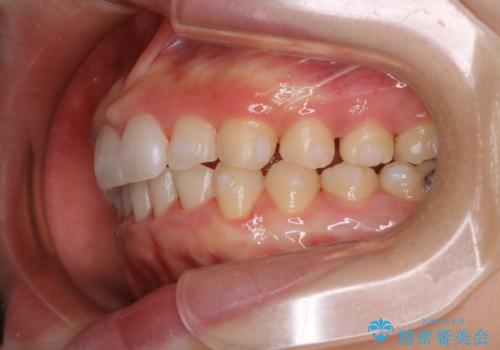

前歯のがたつきとディープバイト:インビザライン治療

- 前歯のがたつきと、噛み合わせが深いことを気にされてご相談にいらした方です。

インビザラインにて治療を行いました。

一般的に、歯冠(歯の長さ)が短い方はインビザライン治療に時間がかかりやすい傾向にあります。

歯の移動量に対して大きなブラックトライアングルもできることなく綺麗に並べることができ、大変喜んでいただけました。